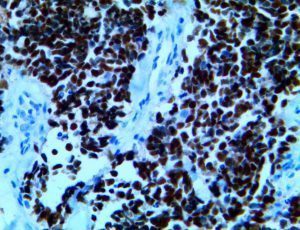

It is the ICU physician who is most likely to witness one of the deadliest manifestations of the abnormal immunological response, the cytokine storm syndrome (CSS). This response is also referred to by some as the cytokine release syndrome (CRS). CSS is characterized by continuous activation and expansion of macrophage and lymphocyte populations, which secrete large amounts of cytokines, causing the cytokine storm. This massive cytokine release is akin to hemophagocytic lymphohistiocytosis (HLH) disease, a syndrome characterized by initial unchecked and persistent activation of cytotoxic T lymphocytes and NK cells.

Clinical and laboratory manifestations of HLH include fever, enlarged liver and/or spleen, neurologic dysfunction, coagulopathy, liver dysfunction, cytopenias (i.e., low levels of erythrocytes, leukocytes, and/or platelets), hypertriglyceridemia, hyperferritinemia, hemophagocytosis, and eventually diminished NK cell activity as the immune system becomes progressively paralyzed. HLH can be familial (primary HLH) or secondary to another disease process (sHLH), such as rheumatic disease, in which it is referred to as macrophage activation syndrome (MAS, characterized by elevated ferritin).